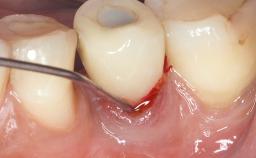

Peri-Implantitis Modified by the Presence of Submucosal Excess Cement: Reconstructive Therapy and a Ten-Year Follow-up

This case outlines the reconstructive therapy by Giovanni Salvi resulting in defect fill and inflammation-free peri-implant soft tissues at 10-year follow up. This case highlights the importance of regular monitoring of implants during supportive therapy.

A 30-year-old female patient was referred to the Department of Periodontology of the University of Bern, Switzerland, by a private dentist. Tooth 45 was congenitally missing and had been replaced with an implant three years prior to the first visit at the Department of Periodontology.